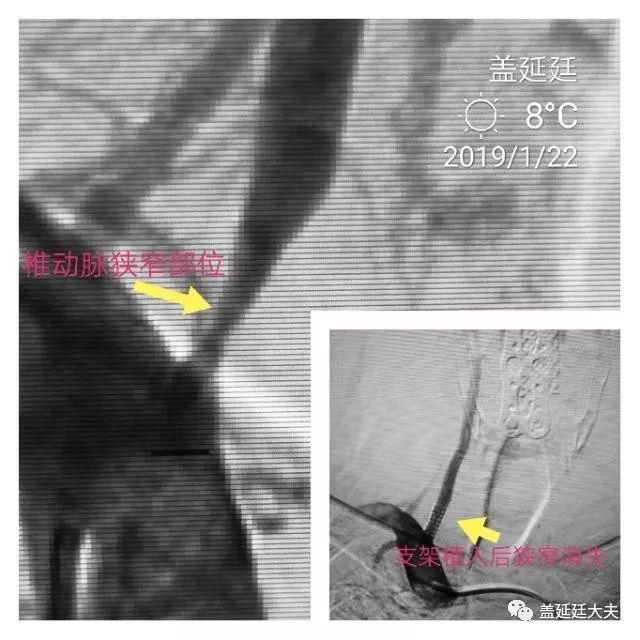

按照既定计划,一大早坐车去了如皋博爱医院。那里安排了一台介入手术。患者老年男性,因为反复头晕头昏检查发现椎动脉重度狭窄。手术顺利,支架植入后椎动脉狭窄部位基本恢复正常官腔。患者感觉头晕明显好转。